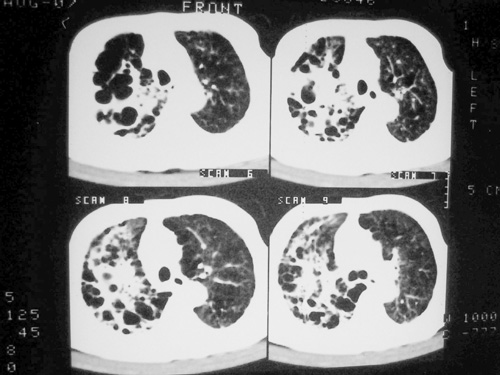

老年男性,70岁。煤矿工人20年。一周前咳嗽、发烧,拍x片考虑矽肺可能。始终咳嗽行ct检查,发现弥漫性病变,似感染但密度很高,细支气管肺泡癌无法排除,请老师给予指点。

一般矽肺多为双肺融合状,团块状高密度结节影.并散在多处小结节影.可这个病人只表现在单肺,并没有融合结节影.一周前的x片没显示大片高密度影,可定位扫描时(图象忽略传了),右肺已经清晰显示大片高密度影.作比较感觉是新病灶.可实际表现又不象,所以才拿来让各位老师看看.

矽肺,两肺间实质炎症,蜂窝肺。

矽肺  两肺间质性炎症伴纤维化(蜂窝肺)

矽肺,tb,蜂窝状影象肺改变。

矽肺合并右肺结核可能性大.右侧少量胸腔积液.